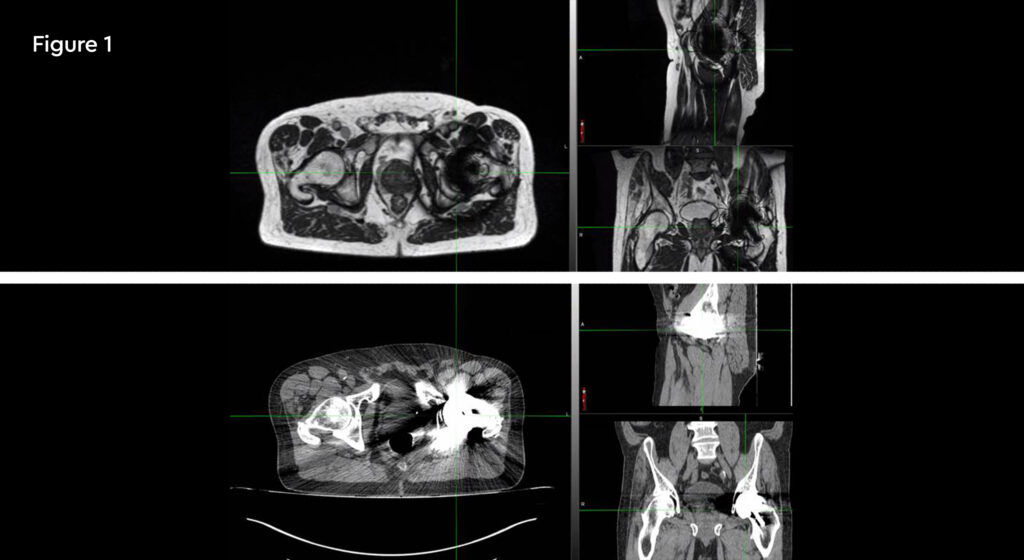

Figure 1: MR and PSMA PET fusion showing recurrence

Figure 2: Contouring target lesion